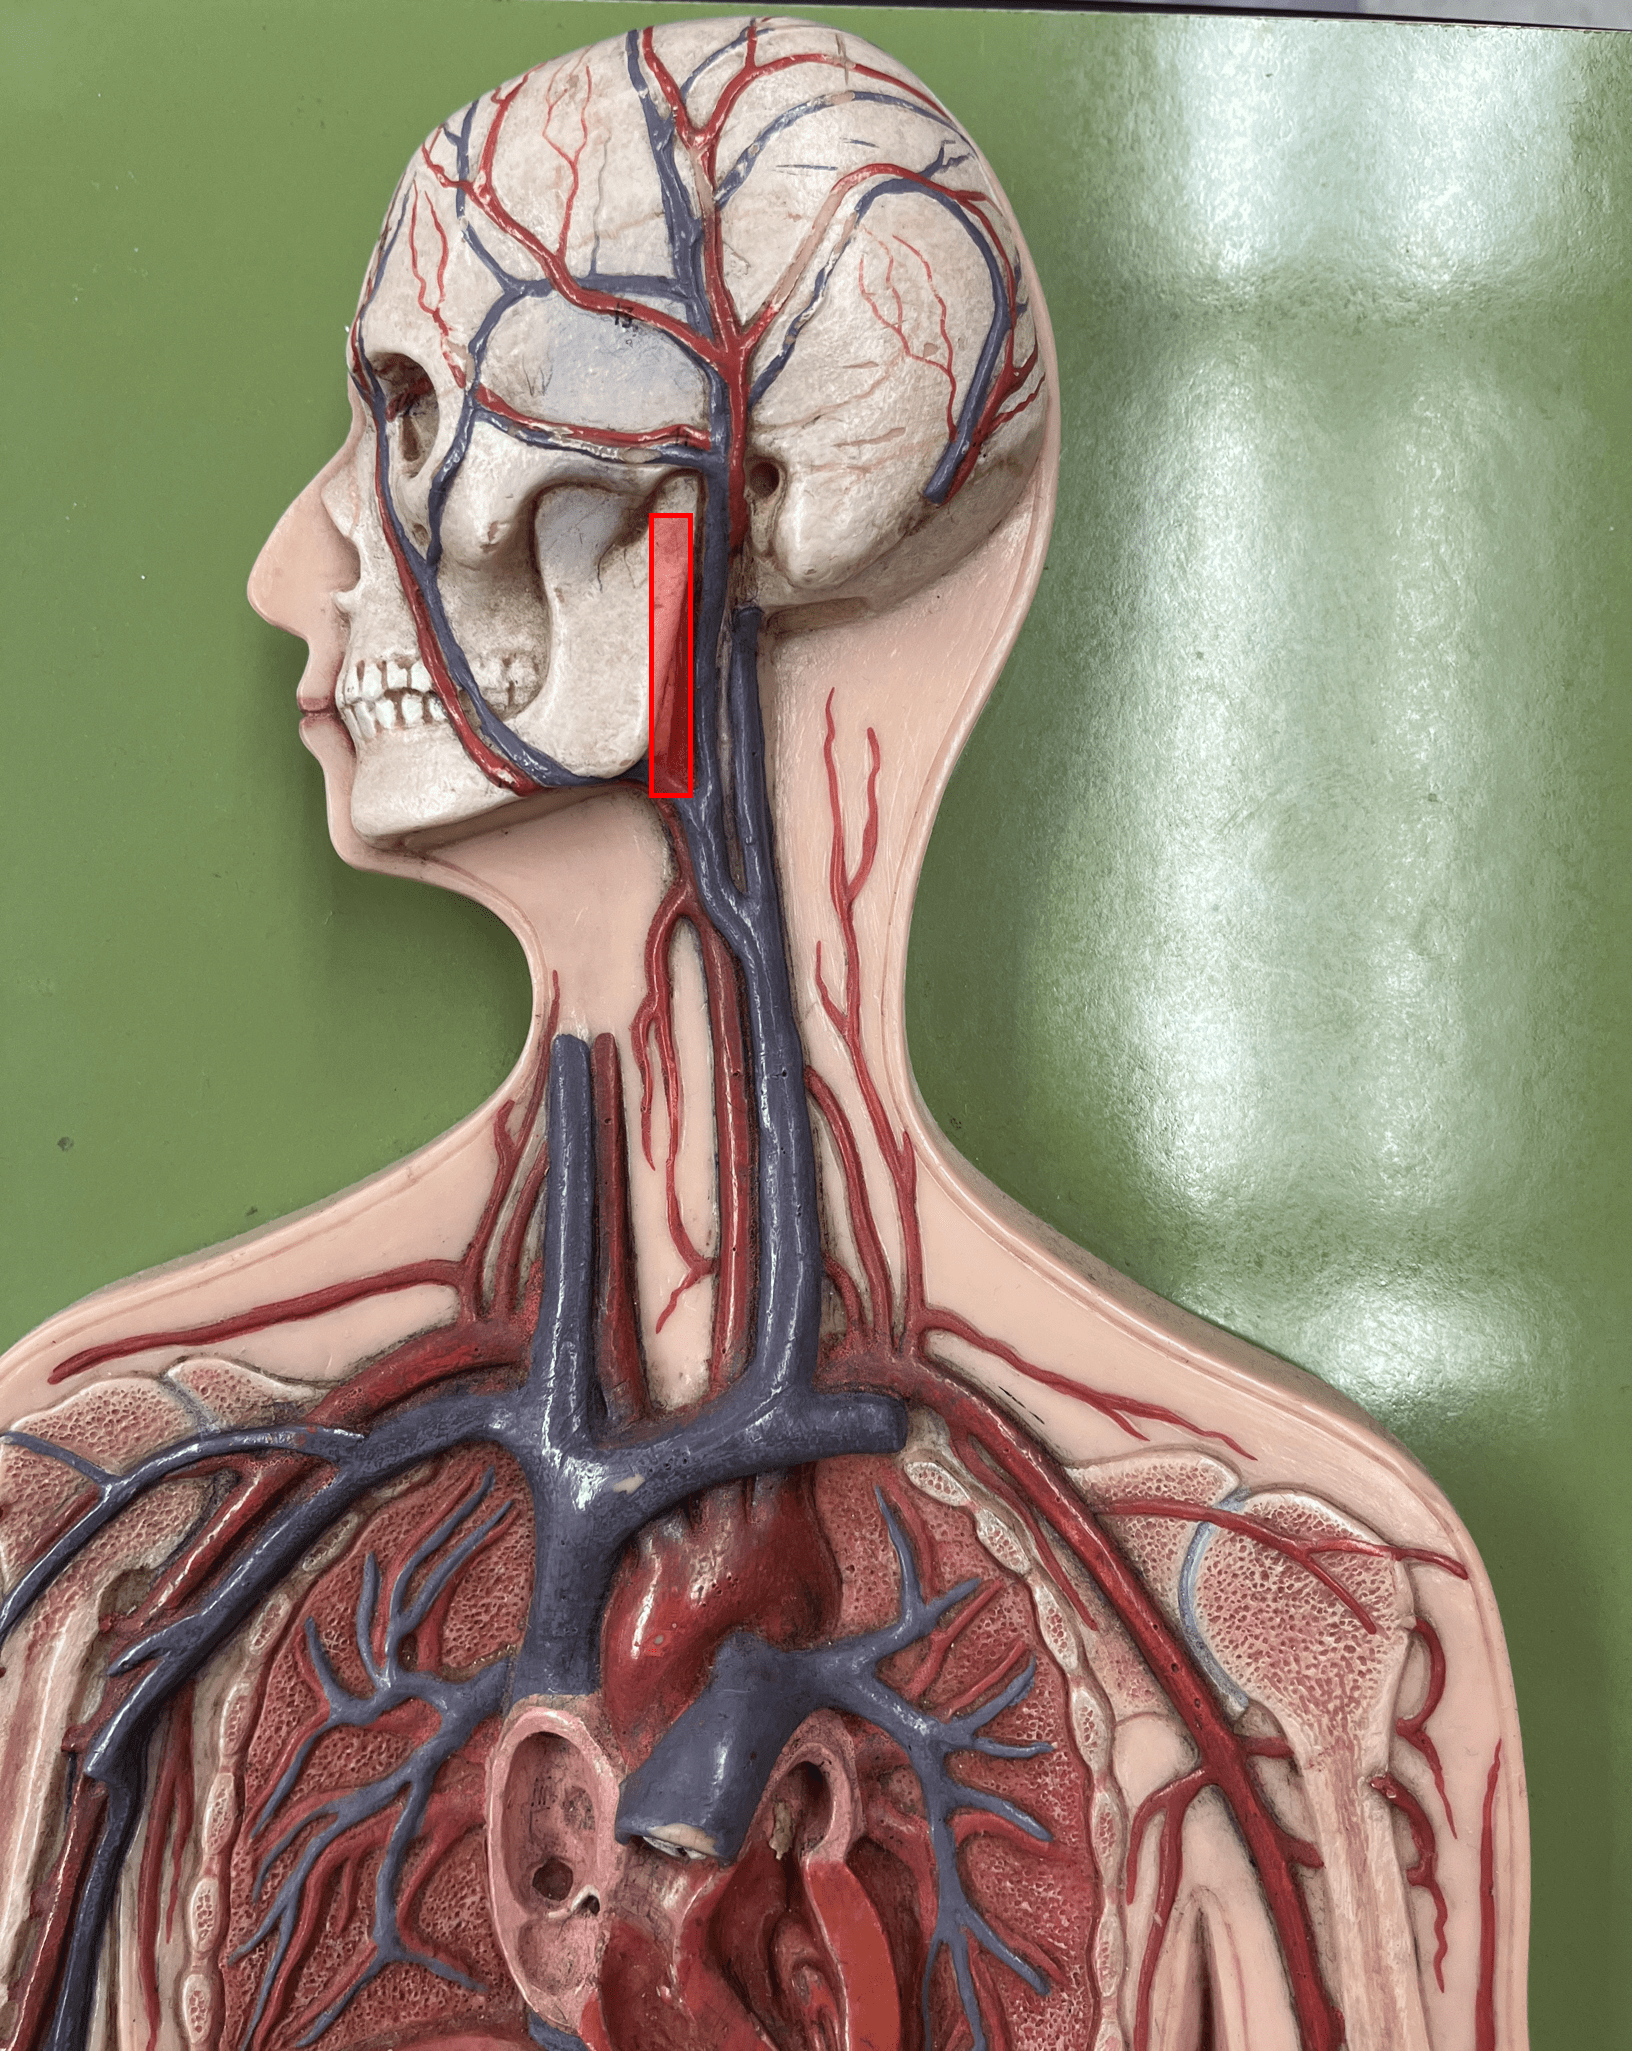

external carotid artery

• Originates from the common carotid artery.

• Supplies the extracranial structures through its branches.

• Laterally, the anteriormost artery of the neck.